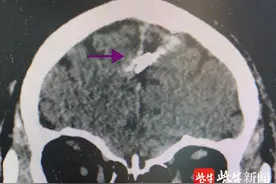

网络图片新安晚报 安徽网(www.ahwang.cn)讯频发癫痫一直找不到原因, CT检查后竟发现脑内有一颗约 5厘米长的钢钉。更让人吃惊的是, 病人杨女士和家人不记得这颗钢钉何时进入脑内。虽然脑内有钢钉, 但杨女士头皮外面光滑平整, 丝毫看不出异样。

我们都清楚癫痫病的原因有很多,但是你绝对想不到一颗钢钉竟然也是导致癫痫的主因。一起去看看是怎么回事吧。半年前,安庆的杨女士有时会感觉头晕头痛,一直没太当回事。谁知这半年内,杨女士又频发癫痫,用了很多药也不见效果。这可急坏了杨女士和家人。